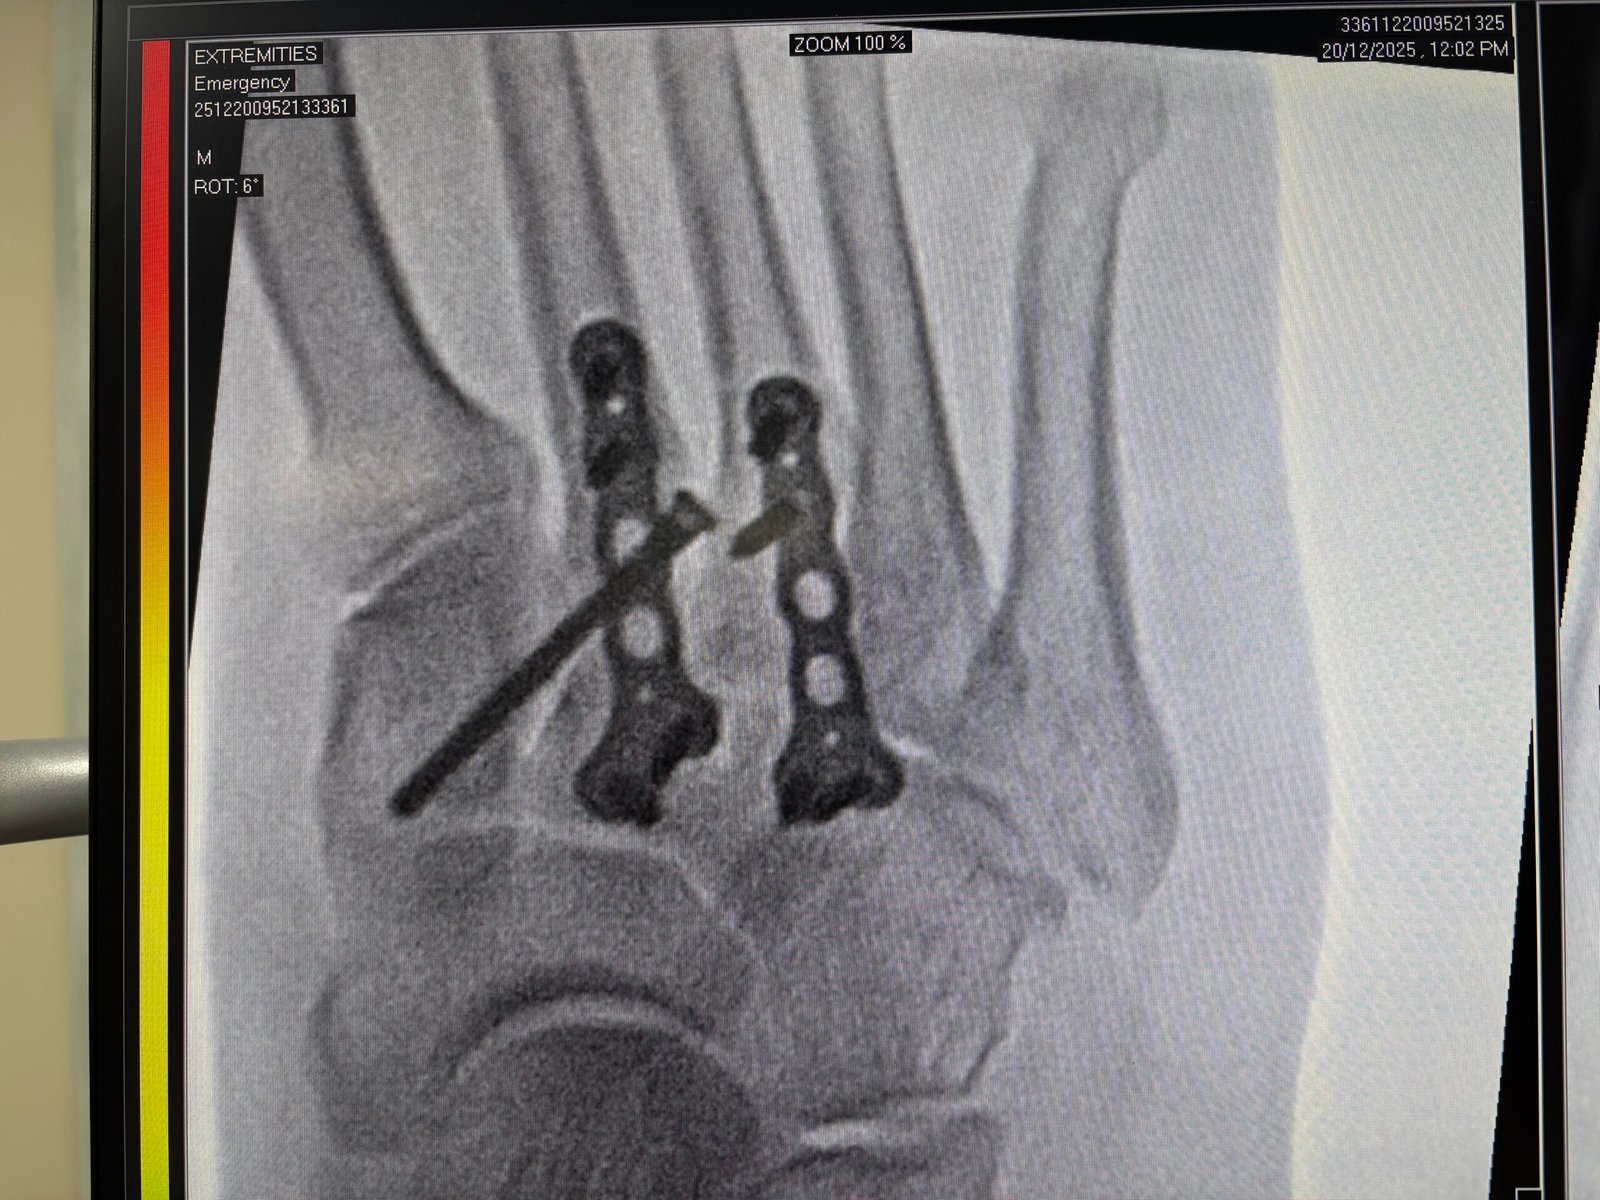

Accident & Trauma Care – Specialized in Bone & Joint Injuries.

Advanced Recovery Solutions. - Hand, Foot & Ankle Specialist:

Precision treatment for injuries, deformities, and chronic pain. - Shoulder & Upper Limb Care:

Known for a results-driven approach that prioritizes minimally invasive techniques and rapid post-surgical rehabilitation.

Over 8,000 successful orthopedic procedures, ranging from complex trauma to total joint replacements.